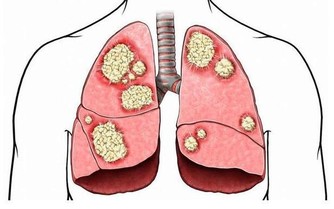

三、氣胸

氣胸是胸外科常見的疾病之一。常常在跑步、拿重物或體力勞動後發生,可發生於無明顯病變的健康人,

尤以體型瘦長的青年多見,也可發生在其他肺部疾病患者。

最典型的症狀是突發的胸痛,多為針刺樣或刀割樣疼痛,持續時間較短,可伴有呼吸困難、刺激性咳嗽等症狀,嚴重者可出現煩躁乃至休克的表現。

如發生氣胸,應馬上臥床休息,充分吸氧,嚴重者需及時就診,由胸外科醫生及時治療。